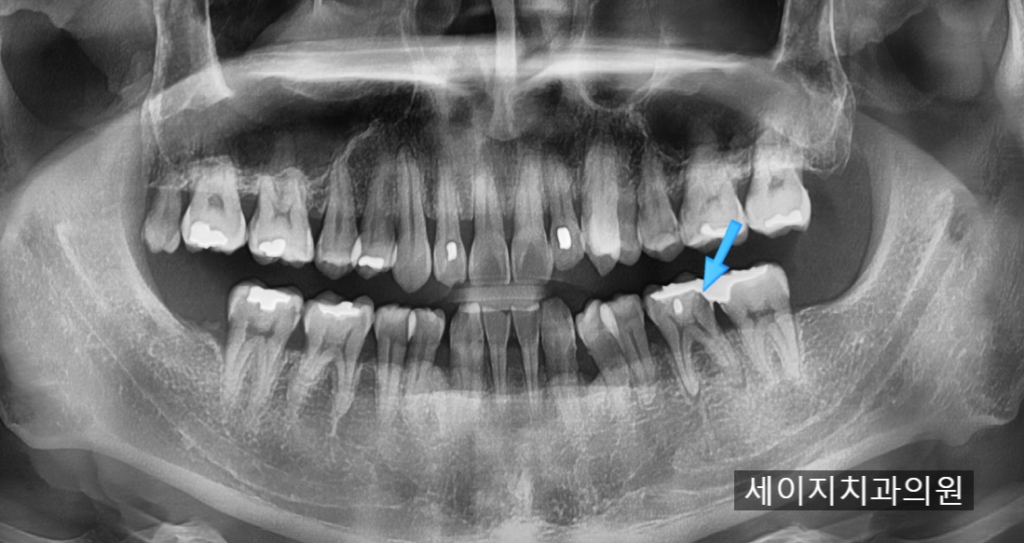

25. 02. 03(엑스레이 검진으로 발견된 이차우식)

금으로 때운 치아의 하방으로 검은 음영이 관찰되었으며, 뿌리쪽으로도 염증이 생기려는 찰나의 모습이 관찰됩니다.